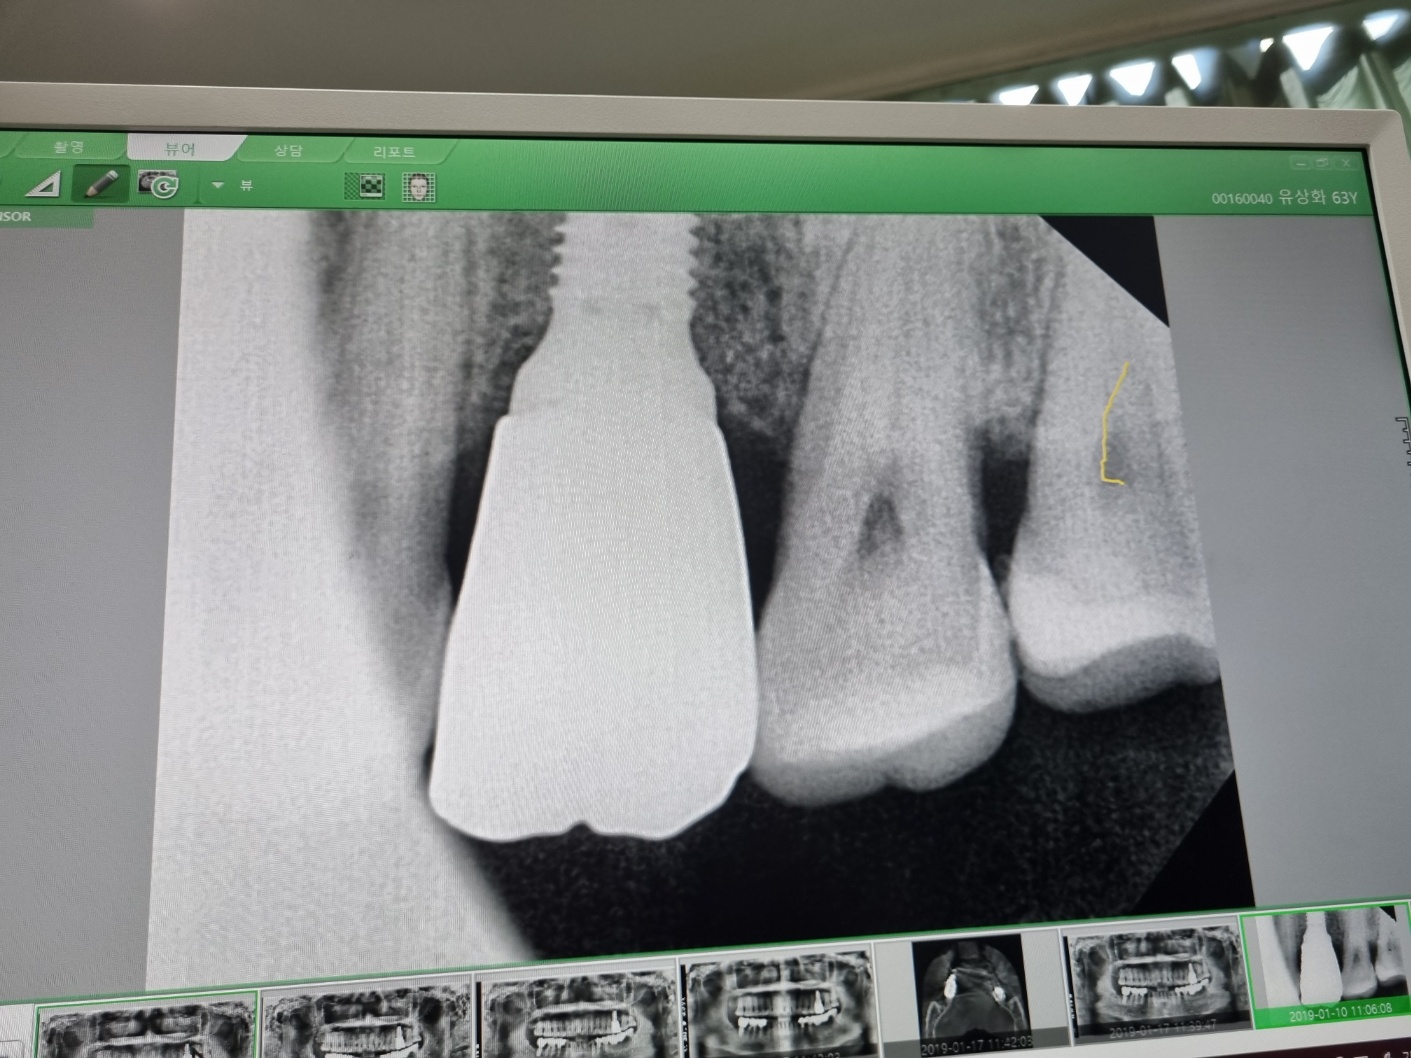

맨 끝에 노란색으로 표시한 부분이

이번에 치료를 받은 사랑니예요

6년 전에 레진치료를 받았는데

다시 문제가 생긴 것인데

나이가 들어가니 치아도 점점 부식이 되는 것이죠

다행히 신경선과는 조금 떨어져서

신경치료까지는 하지 않았는데

그리고 벌써 임플란트를 한 지 5년이 지난

윗치아의 뿌리와 머리 부분을 연결해 주는

나사 부분도 메꾸어 주셨는데요